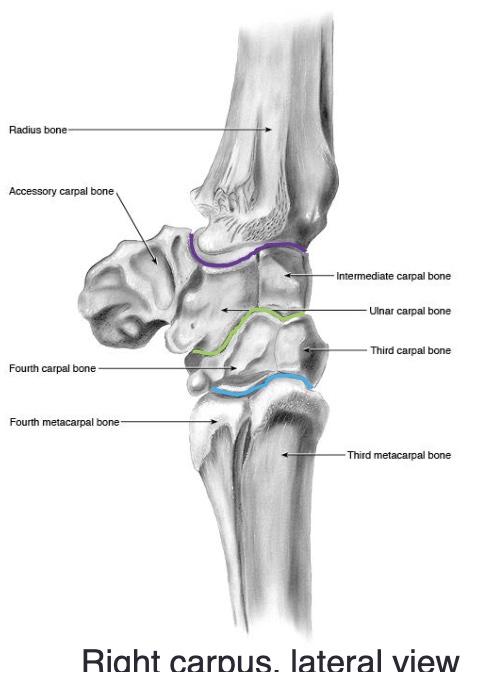

what are the names of the proximal row of carpal bones (medial to lateral)

radial, intermediate, ulnar

what are the names of the distal row of carpal bones (medial to lateral)

2nd, 3rd, 4th

what are the 3 joints of the carpus

radiocarpal (antebrachial) joint

middle/intercarpal joint

carpometacarpal joint

what two joints are the carpus are in communication with e/o

middle/intercarpal joint & carpometacarpal joint

the accessory carpal bone is medial or lateral

lateral